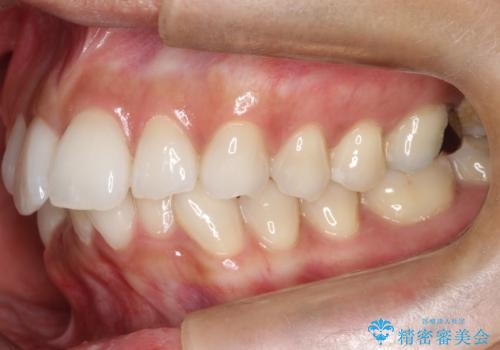

前歯のがたつきをマウスピース矯正で改善。IPRと遠心移動による非抜歯インビザライン治療

精密検査の結果、歯を並べるためのスペースが不足していましたが、抜歯をせずに改善したいというご希望があったため、IPR(歯の側面をわずかに削る処置)と、奥歯を後ろに動かす「遠心移動」を組み合わせる計画を立案。透明なマウスピース装置であるインビザラインを使用し、無理のない範囲でスペースを確保しながら歯列を整えることとしました。

治療では、マウスピースの設計に基づき、奥歯から順に後ろへ移動させる遠心移動を行い、前歯のためのスペースを作りました。同時に、数箇所の歯の間にIPRを施すことで、歯の健康に影響のない範囲で精密に隙間を確保しました。

1年半の治療期間を経て、重なり合っていた前歯はスムーズに整列し、理想的なアーチ状の歯並びへと改善されました。抜歯を行わずに治療を完了したことで、噛み合わせのバランスを維持しながら、審美性を大きく向上させることができました。現在は保定期間に入り、美しい状態を維持されています。